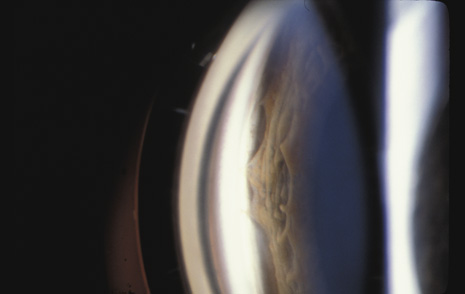

Vitreous Traction Tears

Weidenthal and Schepens76 concluded, from their study of trauma to enucleated pig eyes, that rapid equatorial expansion is responsible for tears at the anterior and posterior borders of the vitreous base. Because the vitreous body is relatively elastic, slow compression of the eye is not deleterious. However, when the eye is rapidly compressed, the vitreous does not have enough time to stretch. As a consequence, there is strong traction at the vitreous base that may cause tears at its anterior and posterior borders.

Scott suggested an alternative mechanism for these tears (J. Scott, personal communication, 1982). He suggested that retrodisplacement of the cornea and aqueous drives the lens-iris diaphragm backward against the anterior vitreous, forcing the vitreous back and pushing the vitreous base away from its adherence to the pars plana epithelium and anterior retina.

Whatever the mechanism, a portion of the vitreous base can be avulsed from the retina and pars plana. The avulsed base looks like a ribbon floating in the vitreous cavity. Closer inspection reveals that the vitreous base remains in contact with the adjacent vitreous cortex, which is also avulsed (Fig. 15). Avulsion of the vitreous base is pathognomonic of blunt trauma and may have considerable medicolegal importance. Unfortunately, in most cases of severe trauma, the vitreous base does not separate cleanly from the retina and pars plana epithelium. It remains adherent, tearing these tissues. The retina can be torn along the posterior margin of the vitreous base, or the nonpigmented pars plana epithelium can be torn along the anterior margin of the vitreous base, or both can be torn simultaneously. Similarly, if the vitreous is strongly adherent to either lattice degeneration or a vitreoretinal scar posterior to the vitreous base, a posterior flap tear may occur.77 Any of these tears can cause a retinal detachment.

Fig. 15. The avulsed vitreous base remains contiguous with the adjacent vitreous cortex.